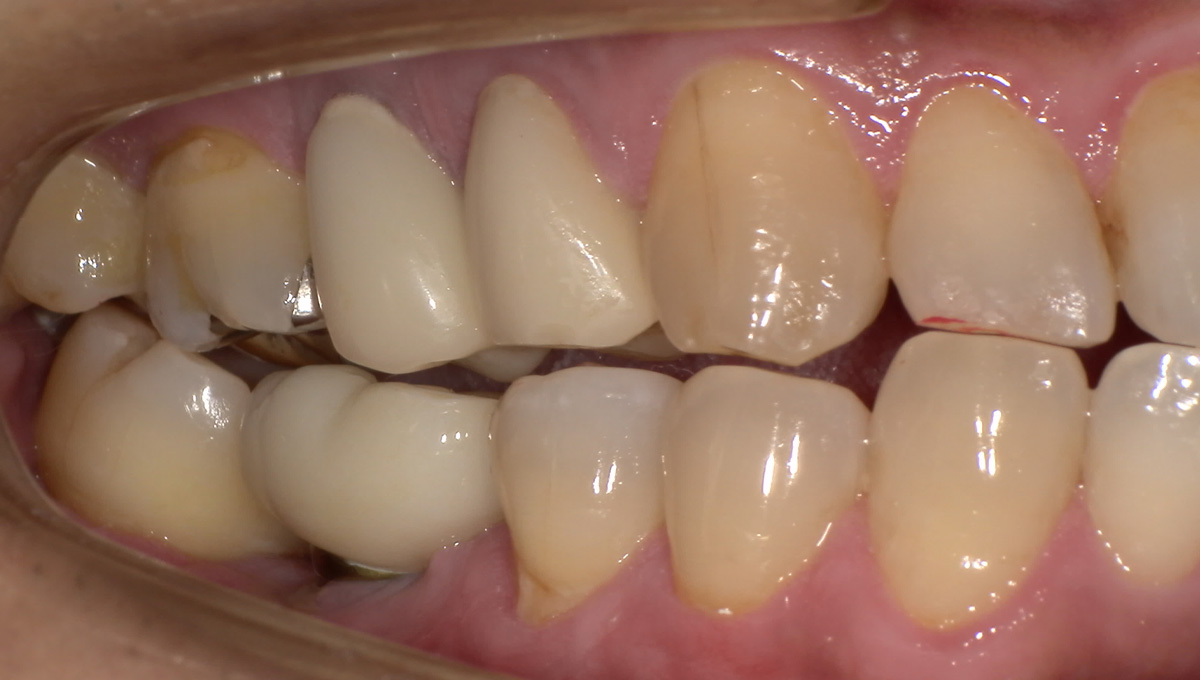

抜歯した箇所にインプラント治療を行った例

術前・術後の比較

インプラント手術から3ヵ月後、型どりをして、仮歯を製作しました。

レントゲン画像 -

仮歯の調整期間を経て、セラミックの歯が入りました。

レントゲン画像 治療前 インプラント治療後